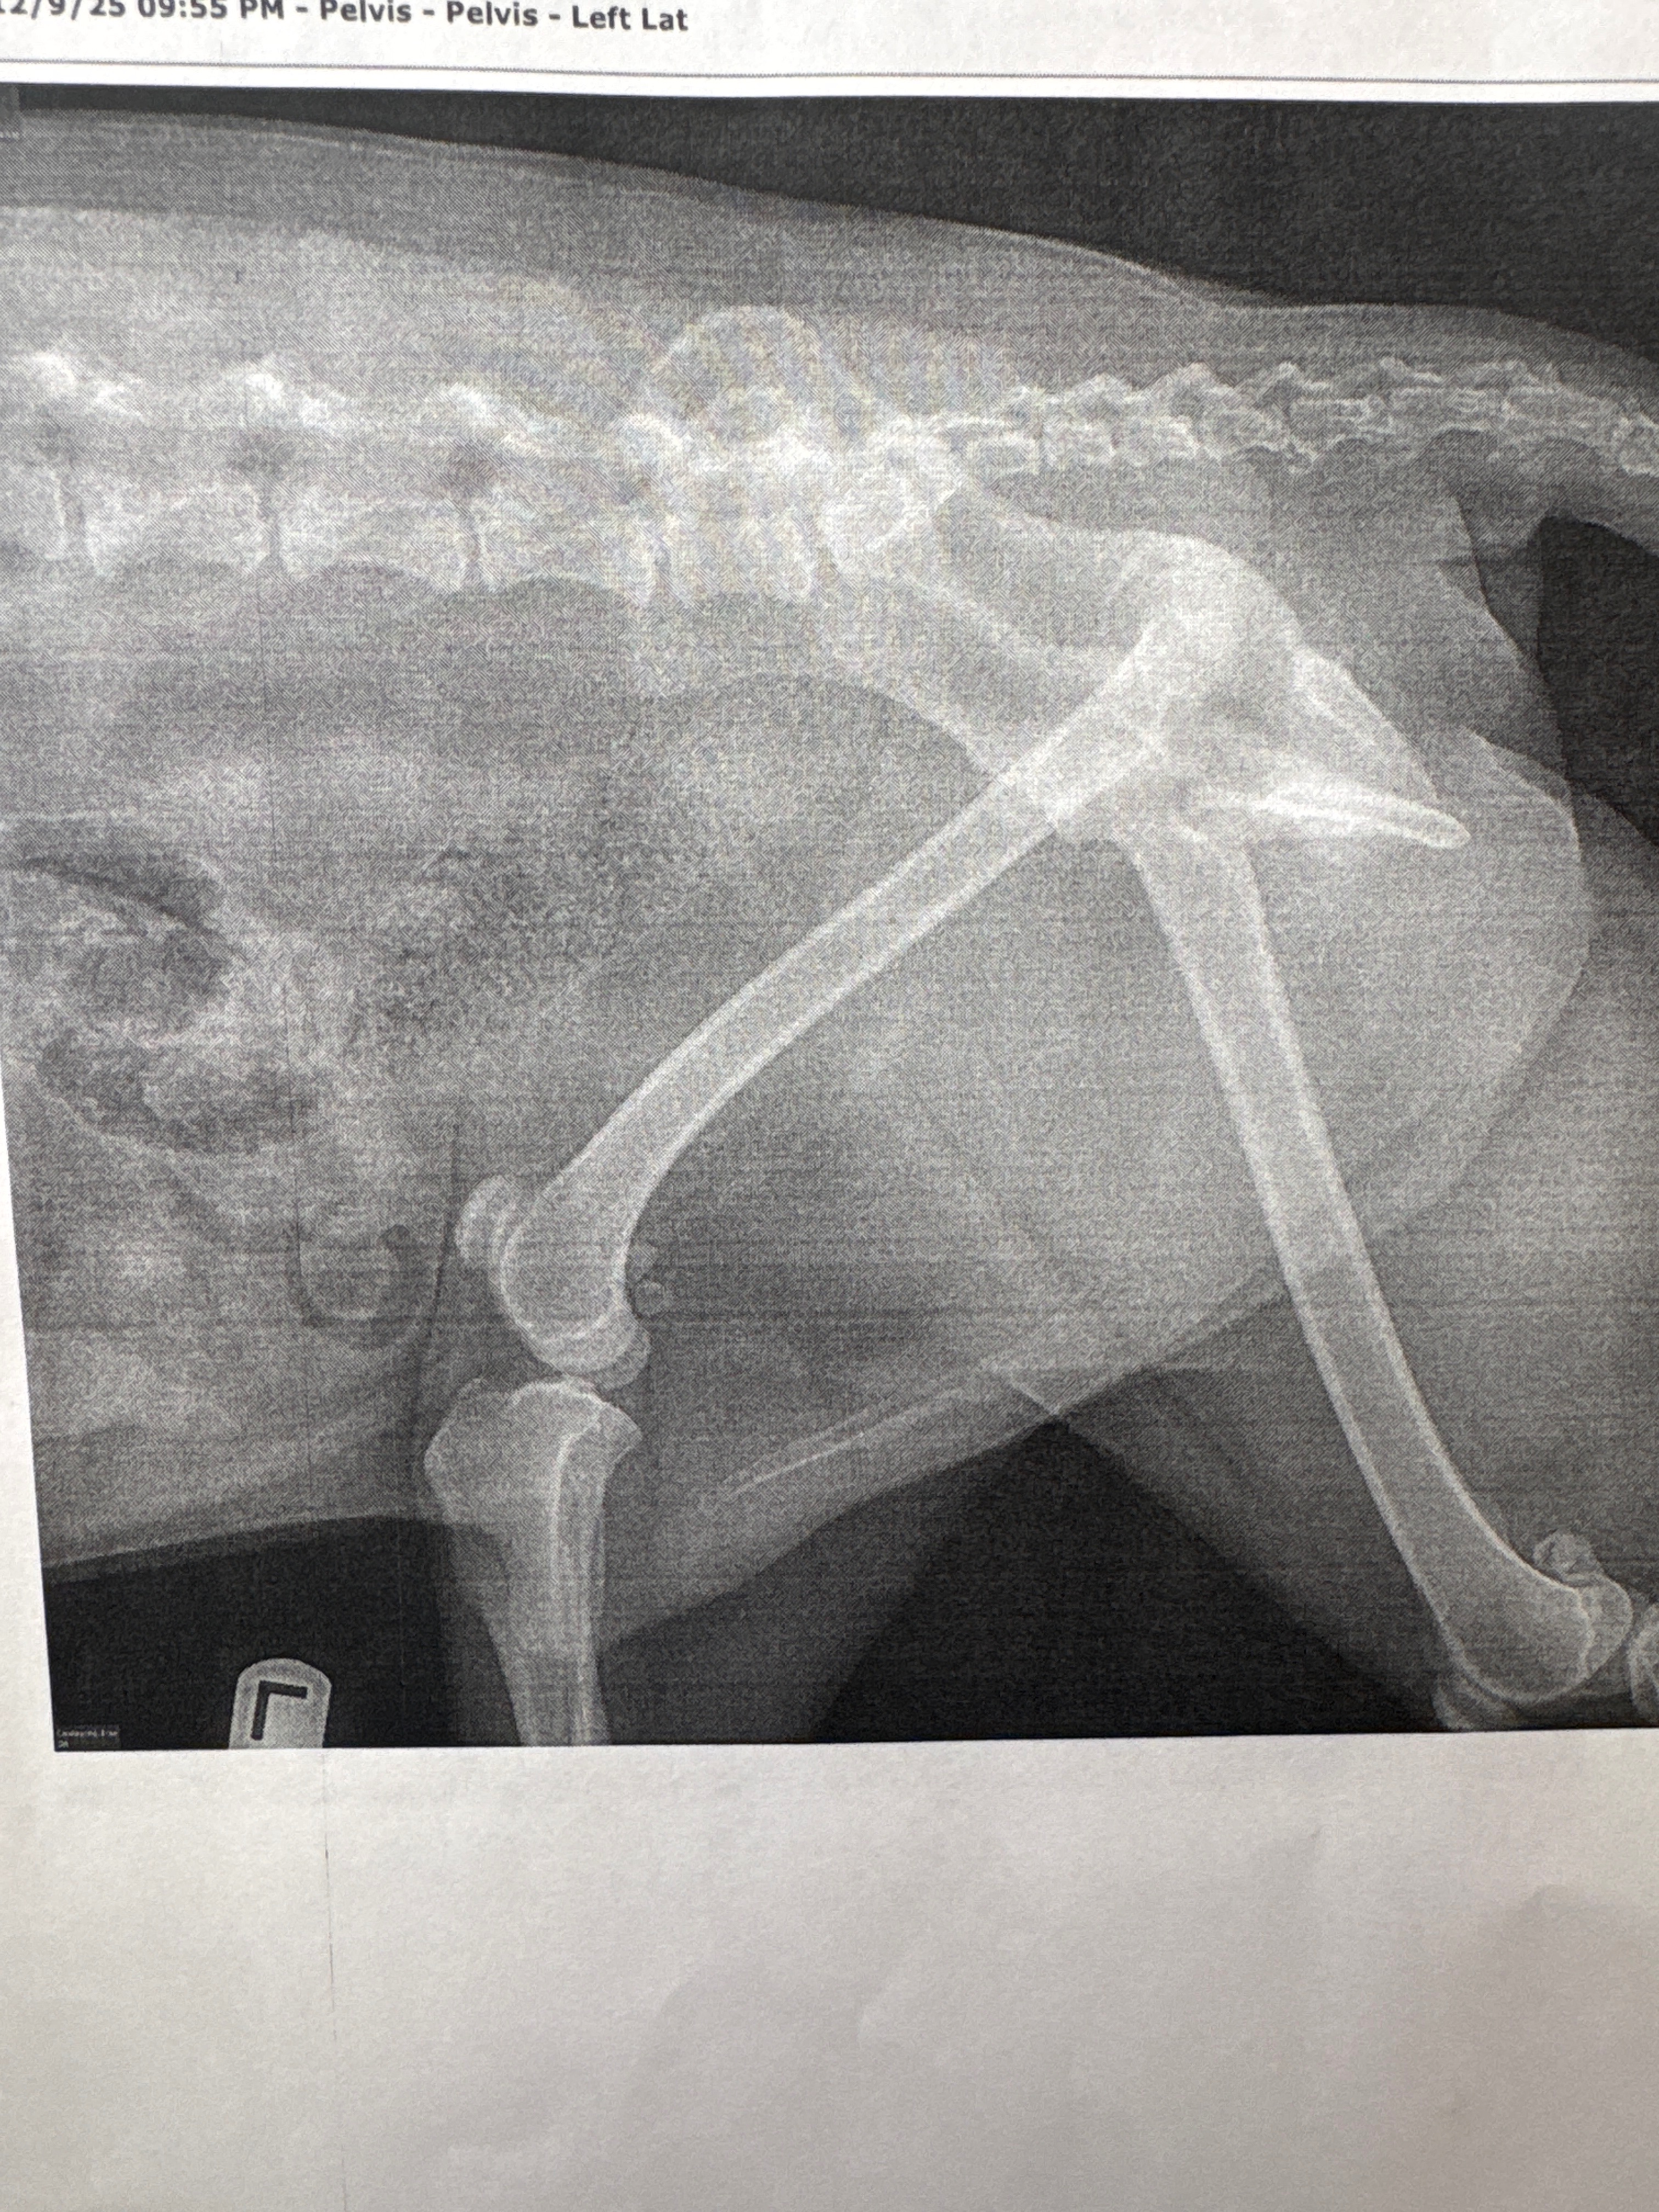

Felix is alive, but he suffered a broken hip in two places and now needs major surgery to recover. The veterinary team will need to place screws, a plate, and other hardware to help his hip heal correctly. This isn’t the first time Felix has faced something like this. He was hit once before in 2018, but we couldn’t afford surgery then. This time, we’re determined to give him the best chance at a full recovery. However, the costs for surgery, medications, and follow-up appointments are overwhelming. Felix is the sweetest boy, always patient with our daughter and still so gentle and loving, even after all he’s been through. We’re doing everything we can to cover this unexpected expense, but we can’t do it alone. Any support, whether it’s a donation, sharing our story, or sending kind words, would mean the world to us. Thank you for helping Felix heal and for being part of his journey back home. ❤️❤️